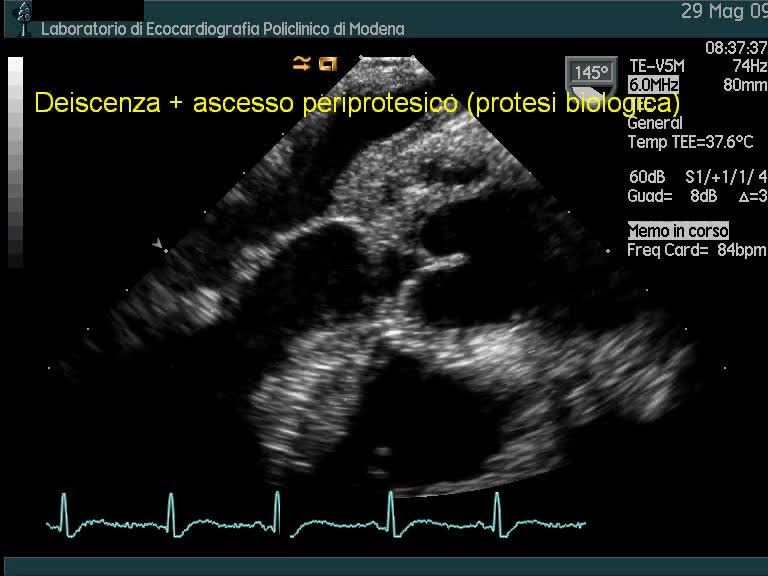

Ascesso periprotesico e distacco di protesi aortica biologicaAutore: Andrea Barbieri

Categoria: Videoalbum

Parole chiave: diagnosi ecotee endocardite protesi -